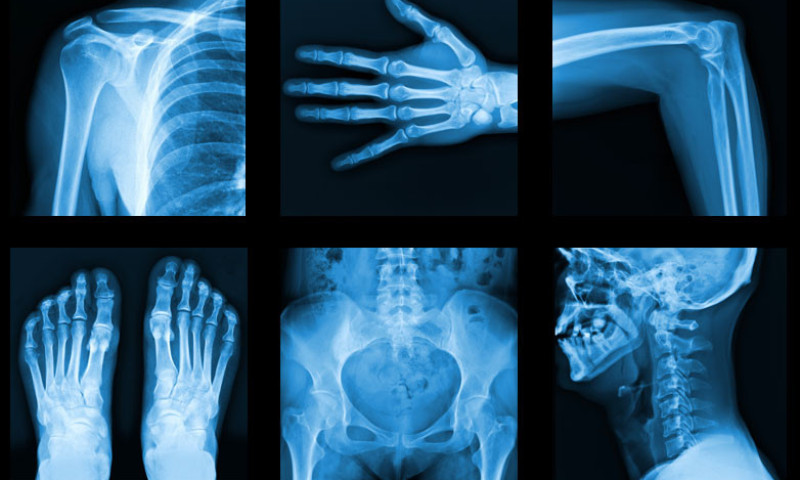

‘एक्स–रे’ शब्द हाम्रो जनबोलीको सामान्य शब्द जस्तै भइसकेको छ । यो शब्द नबोल्ने वा नसुन्ने मानिस बिरलै होलान । तर कमैलाई मात्र यसको बारेमा वास्तविक जानकारी हुनसक्छ । एक्स–रे र एक्स–रे प्रविधिको बारेमा जान्नैपर्ने केही तथ्यहरु :

एक्स–रे एक प्रकारको विद्युत चुम्बकीय किरण (इलेक्ट्रोम्याग्नेटिक रेडिएसन) हो । अर्को शब्दमा भन्नुपर्दा,एक्स–रे सुर्यको प्रकाश जस्तै तर हजारौं गुणा बढी आवृति र शक्ति भएको अदृश्य विकिरण हो ।

एक्स–रे चिकित्सा प्रविधिमा विभिन्न रोगहरुको निदान (रेडियो–डायग्नोसिस) एवं उपचार (रेडियोथेरापी) गर्न प्रयोग गरिन्छ । यस बाहेक एयरपोर्ट,मेट्रो टेन आदिमा सामानहरुको सुरक्षा चेकजाँच र उद्योगहरुमा पनि एक्स–रे प्रयोग हुन्छ ।

साधारण एक्स–रे मेसिन,मेमोग्राफी, सिटि स्क्यान, सिआर्म, क्याथ ल्याव, डेन्टल एक्स–रे, बोन डेन्सिटोमेट्री (डेक्सा स्क्यान) जस्ता निदानात्मक (डायग्नोस्टिक) उपकरणहरुमा एक्स–रे प्रयोग हुन्छ । त्यस्तै, क्यान्सरको उपचार (रेडियोथेरापी) का लागि प्रयोग गरिने लिनियर एसेलेरेटरले पनि उच्च शक्तिको एक्स–रे उत्पन्न गर्दछ । ‘साइबर नाइफ’ भन्ने रेडियोसर्जरी प्रविधि लिनियर एसेलेरेटरमा आधारित अत्याधुनिक रेडियोथेरापी प्रविधि हो,जसमा कुनै चिरफार बिना शरीरको भित्री भागमा रहेको ट्युमरको उपचार गरिन्छ ।